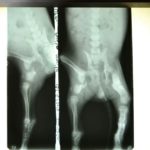

Francesca took the pup to her vet, who x-rayed the pelvis and said that nothing could be done for her. After two weeks of rest at the clinic, the puppy was somehow up and moving about, even playing!

Dr. Calderon took new x-rays, and her injuries are consolidating, so he recommended not to do anything for the moment. The puppy may need an amputation later when she has grown.

Update: Dr. Jim Bader examined Mouse and agreed that she is healing well and that she should not be operated on. Her left knee is fused and she will have a peg leg and be unable to bend it. He feels that no amputation will be necessary as she weight bears with no apparent pain or discomfort. Her skin and coat are improving and she now looks fluffy and healthy.